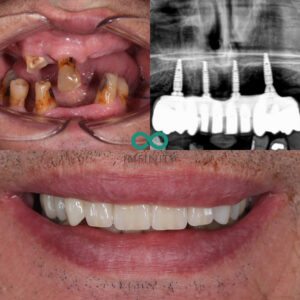

To achieve this, we placed four Straumann Dental Implants to support a full-arch replacement. This approach allowed us to create a secure, natural-looking smile tailored to him. The results are truly remarkable. From the pictures, you can see how this smile enhances his appearance while retaining his unique character.

On Christmas Eve, as we revealed his new smile, he was visibly moved. He shared that his late mother’s final wish had been for him to have perfect teeth, and he felt she would have been so proud of him. It was a powerful reminder of how important a smile can be—not just for appearance, but for self-esteem, relationships, and those precious family moments.